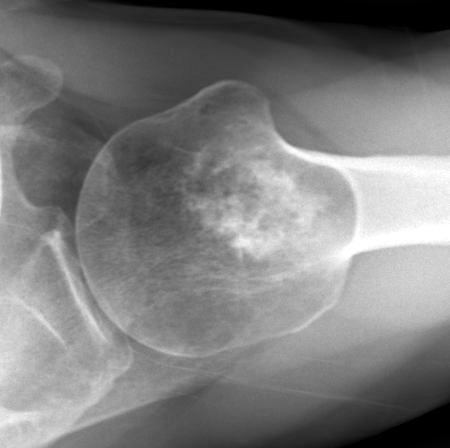

Endosteal scalloping

Large, central enchondroma

Enchondroma versus chondrosarcoma

- deep endosteal scalloping (>2/3 cortical thickness)

- cortical destruction

- soft tissue mass